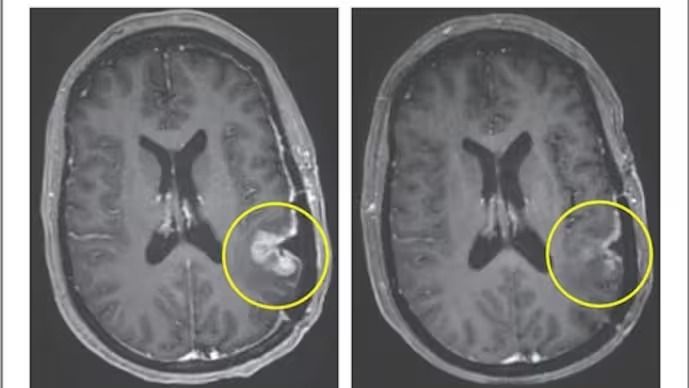

৫ দিনেই অদৃশ্য ব্রেন টিউমার! আশা জাগাচ্ছে ক্যান্সারের নয়া ওষুধThe New England Journal of Medicine-এ প্রকাশিত ছবি

এই ট্রায়ালে ৩ জন রোগী অংশ নেন। তাদের বয়স ছিল ৫৭ থেকে ৭৪ বছরের মধ্যে। তারা আগে রেডিয়েশন ও কেমোথেরাপি নিয়েছিলেন। ফলাফলে দেখা যায়, একজন রোগীর টিউমার দ্রুত কমে, কিন্তু তা স্থায়ী হয়নি। আর একজনের ক্ষেত্রে ৬০ শতাংশের বেশি টিউমার কমে এবং তা ছয় মাসের বেশি সময় স্থায়ী হয়। তৃতীয় রোগীর ক্ষেত্রে মাত্র ৫ দিনের মধ্যে প্রায় সম্পূর্ণ টিউমার সঙ্কুচিত হয়ে যায়।